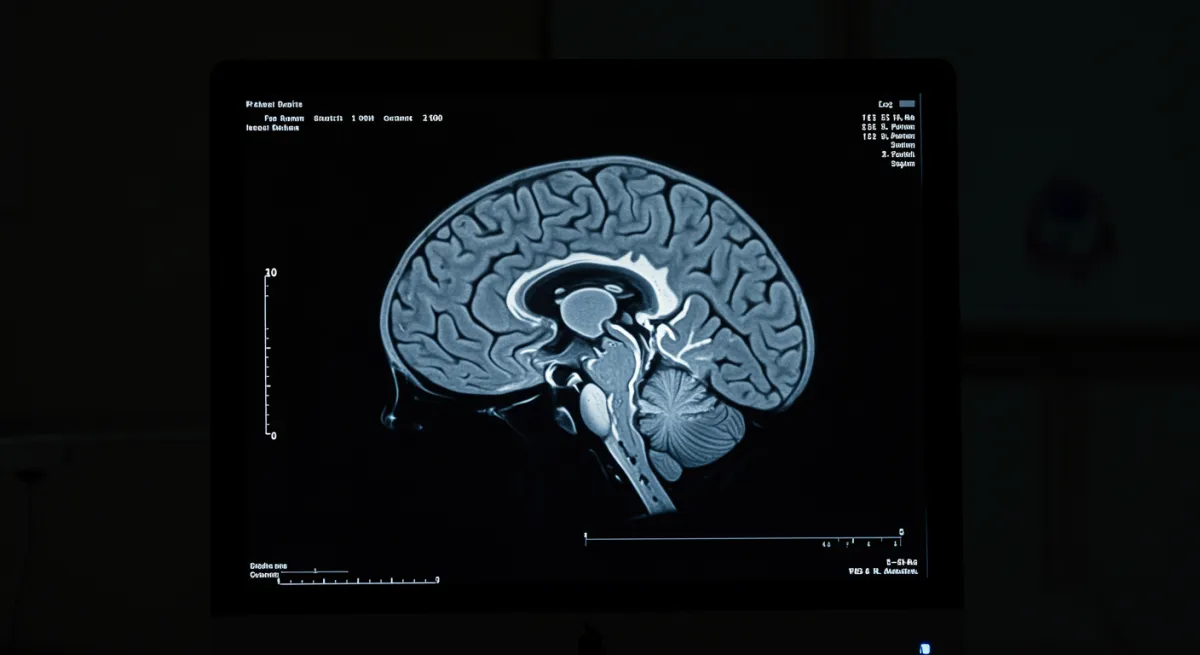

Chronic stress disrupts the brain’s stress response system (HPA axis), causing cortisol dysregulation and inflammation that damages the hippocampus - the brain’s memory and mood center. This creates a cascade of brain changes that lead to depression. Key mechanisms:

The research shows that chronic HPA axis activation interacts with inflammatory pathways and generates oxidative stress, specifically targeting the hippocampus - a brain region crucial for memory, learning, and mood regulation. This neuroinflammation damages hippocampal neurons and disrupts neuroplasticity, the brain’s ability to adapt and form new connections.